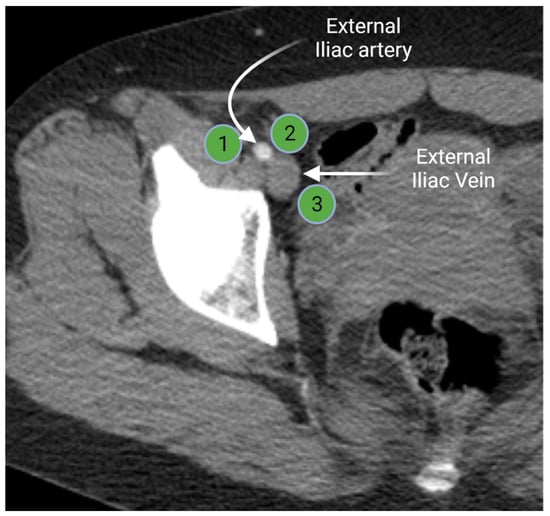

2.1.2. Iliac Lymph Nodes Anatomy